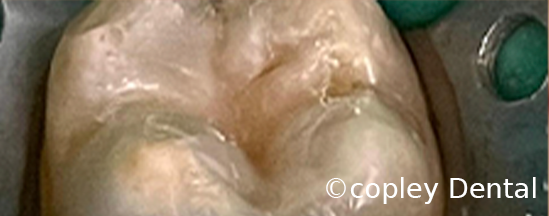

Cosmetic tooth colored white dental filling using composite material to restore the original anatomical structure of the tooth.